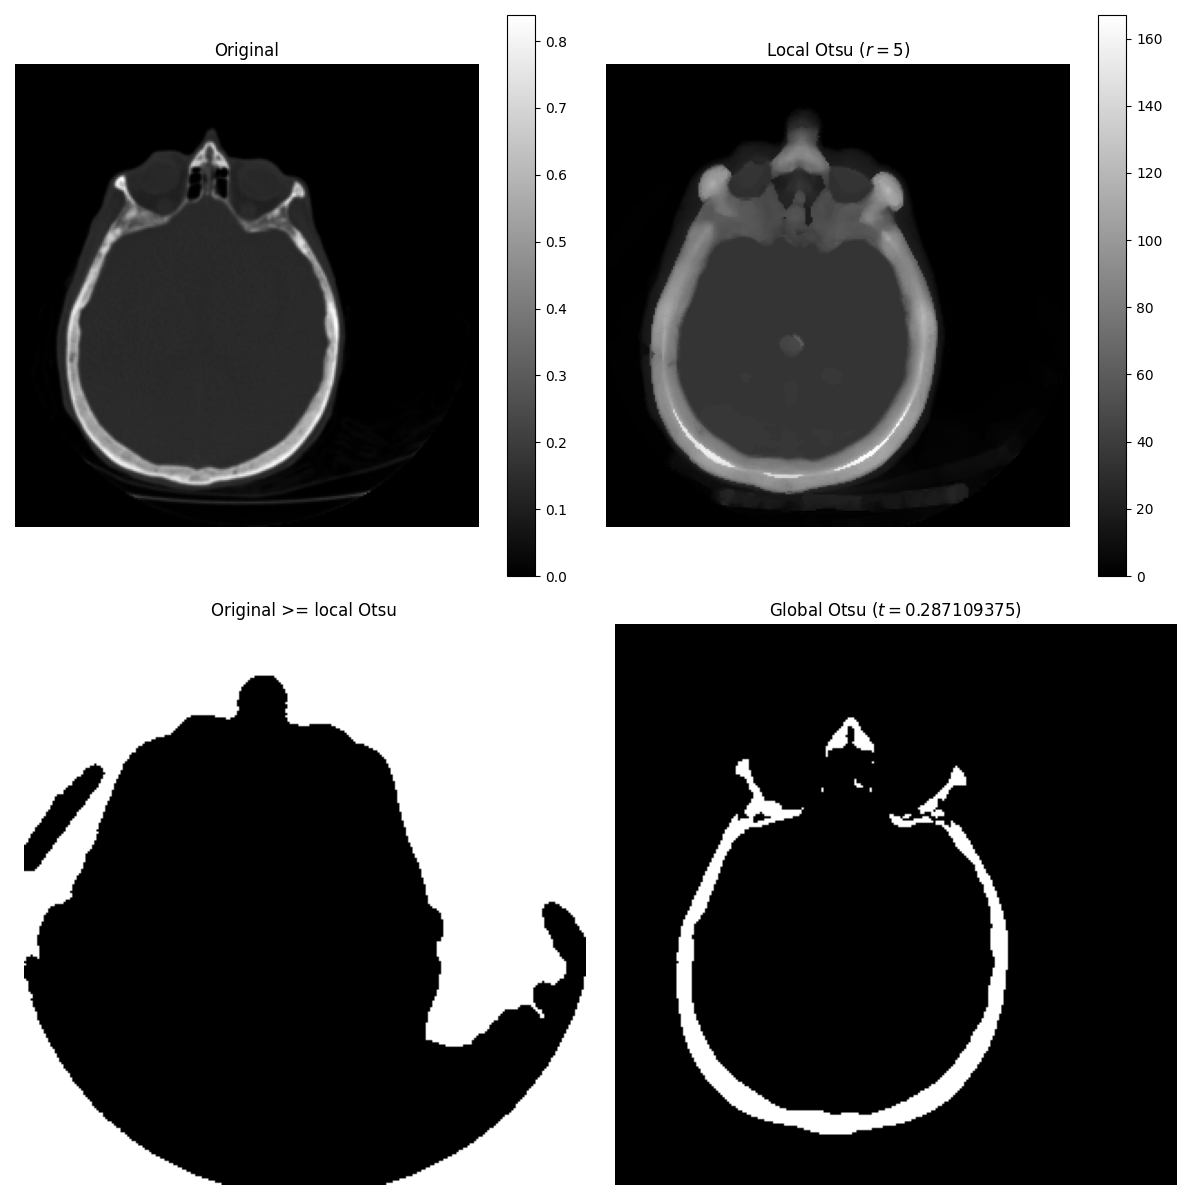

Otsu 阈值法 [5] 可以通过使用局部灰度分布进行局部应用。在下面的示例中,对于每个像素,通过最大化由结构元素定义的局部邻域中两类像素之间的方差来确定一个“最优”阈值。

该示例将局部阈值处理与全局阈值处理进行了比较,后者由 skimage.filters.threshold_otsu() 提供。请注意,前者比后者慢得多。

下面的示例执行相同的比较,这次使用的是3D图像。

brain = exposure.rescale_intensity(data.brain().astype(float))

radius = 5

fig, axes = plt.subplots(nrows=2, ncols=2, figsize=(12, 12), sharex=True, sharey=True)

slice_index = 3

fig.colorbar(ax[0].imshow(brain[slice_index], cmap=plt.cm.gray), ax=ax[0])

ax[0].set_title('Original')

fig.colorbar(ax[1].imshow(t_loc_otsu[slice_index], cmap=plt.cm.gray), ax=ax[1])

ax[1].set_title(f'Local Otsu ($r={radius}$)')

ax[2].imshow(brain[slice_index] >= t_loc_otsu[slice_index], cmap=plt.cm.gray)

ax[2].set_title('Original >= local Otsu')

ax[3].imshow(glob_otsu[slice_index], cmap=plt.cm.gray)

ax[3].set_title(f'Global Otsu ($t={t_glob_otsu}$)')